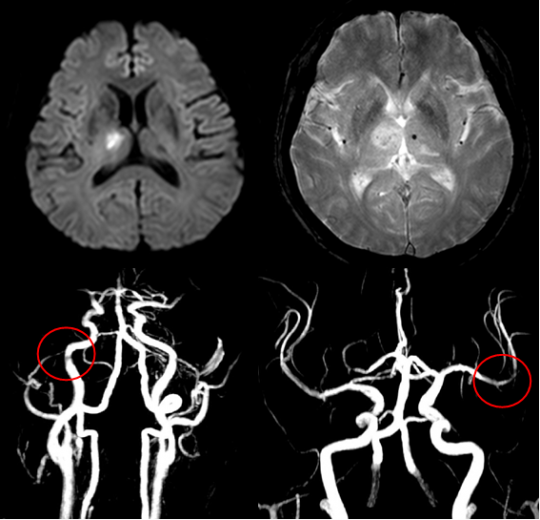

먼저, 뇌경색이 무엇인지 간단히 설명드리고자 합니다. 뇌경색은 뇌의 일부에 혈액 공급이 차단되면서 발생하는 질환입니다. 이로 인해 해당 뇌 영역이 손상되고, 다양한 증상이 나타납니다. 뇌경색은 크게 허혈성 뇌경색과 출혈성 뇌경색으로 나뉘며, 허혈성이 더 일반적입니다. 이 증상은 초기 발병 시점에 따라 치료의 효과가 크게 차이가 납니다.